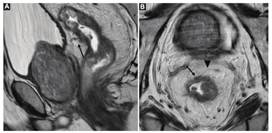

Se debe determinar con certeza si la lesión se encuentra a nivel rectal o en el colon sigmoides, ya que en ambos casos existe un abordaje quirúrgico distinto3. Uno de los métodos más utilizados por las guías internacionales para la definición de tumor de recto es la medición de la distancia entre la porción distal de este y el margen anal, considerando a todos aquellos tumores ubicados a una distancia ≤ 15 cm del margen anal como tumor rectal. A su vez, se los subclasifica en tumores de recto superior, medio y/o inferior (Fig. 2)3),(4),(5. El recto es un órgano con una porción intraperitoneal y otra extraperitoneal, que pueden ser diferenciadas mediante la identificación de una fina membrana hipointensa en T2 correspondiente a la reflexión peritoneal anterior. Esta suele visualizarse en el plano sagital y une las vesículas seminales en el hombre y el fondo de saco de Douglas en la mujer, con la cara anterior del recto medio (Fig. 3)3,6. Por encima de esta, el peritoneo recubre las caras anterior y lateral del recto superior y la cara anterior del recto medio, mientras que el recto inferior es completamente extraperitoneal6. A su vez, la FMR rodea completamente al mesorrecto por debajo de la reflexión peritoneal y por su caras laterales y posteriores por encima de esta3 (Fig. 4).